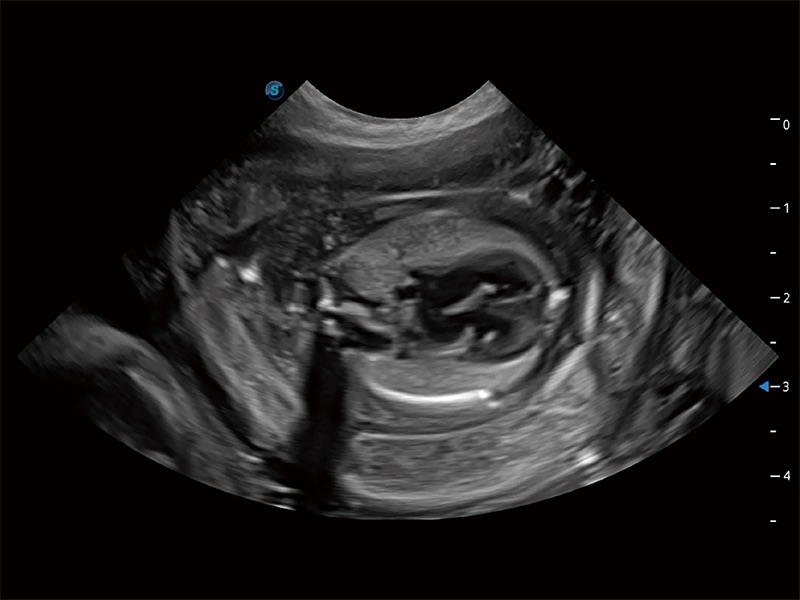

动物是人类最亲密的朋友和最值得信赖的伙伴。诸侯快讯官网也一直致力于探索动物专用的超声影像解决方案。全新推出的ProPet系列,是诸侯快讯官网在动物超声影像智能化、专业化、精准化的一次跨越式革新。动物不能用言语来表述自己的不适,通过超声影像,ProPet系列搭建了动物医生与不同物种沟通的“桥梁”,为动物医生注入了“治愈之力”。 ProPet 80 是诸侯快讯官网匠心打造的一款高端动物专用彩超,采用性能卓越的全新硬件架构,极大提升超声系统的运行效率和数据处理能力,帮助动物医生从容应对日益增多的挑战性病例和日益多样化的临床需求。

高性能和先进的临床应用工具可以为动物医生提供临床信心。ProPet 80 搭载了先进的腹部和浅表应用工具,帮助医生在日常临床实践中发挥前所未有的作用。

ProPet 80 专为动物医生设计,对不同的动物体型和生理结构作出了针对性的优化。通过动物影像专用软件,可满足个性化的应用需求,帮助动物医生获得更精确的诊断数据。

ProPet 80 全新的动物超声智能软件和丰富的探头群,为动物医生提供了高清晰度和精细分辨率的图像,无论在宠物、马科、畜牧还是实验室动物等应用中都可以轻松应对,为您的日常工作带来满意的体验。